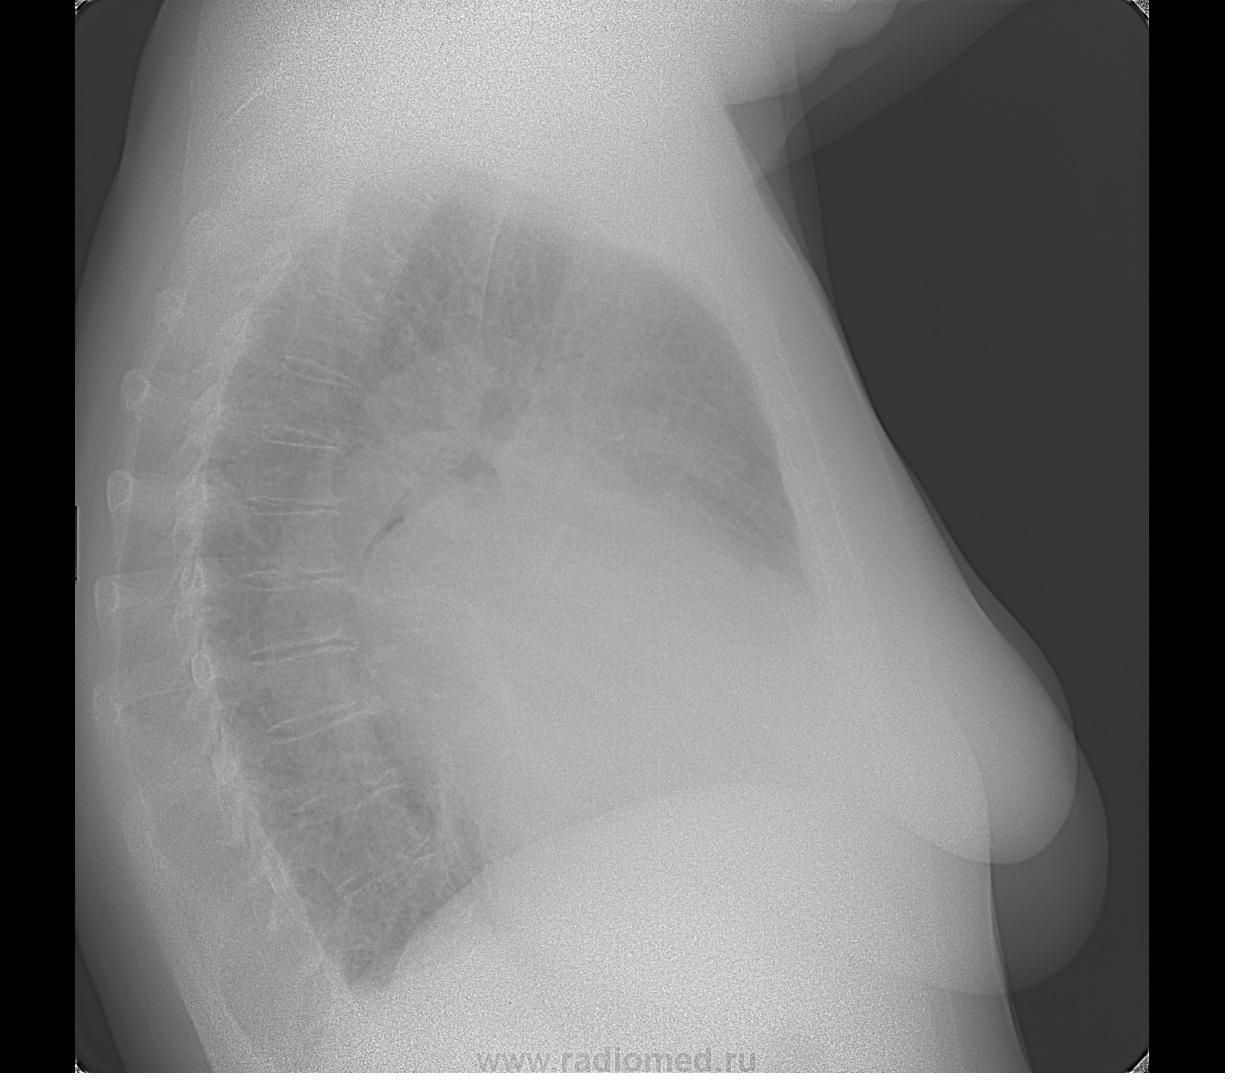

Пол пациента: Женский пол Тип патологии: Другое Область исследования: Средостение и сердце Методы исследования: Rg https://radiomed.ru/sites/default/files/styles/case_slider_image/public/user/5536/2_1.jpg?itok=5gIAUs0v https://radiomed.ru/sites/default/files/styles/case_slider_image/public/user/5536/3_1.jpg?itok=DAF4_PHJ ID:21733 Чт, 14/06/2012 - 22:44 #1 И.Бондаренко Не на сайте Был на сайте: 1 день 12 часов назад Зарегистрирован: 13.09.2011 - 22:55 Публикации: 9213 Отдайте функционалам. Это их хлеб. Чт, 14/06/2012 - 22:46 #2 Mitkampfer Не на сайте Был на сайте: 11 лет 6 месяцев назад Зарегистрирован: 27.07.2010 - 07:43 Публикации: 1454 уже) Не ограничивайте свою мысль Живешь пока учишьсяEcrasez l’infame